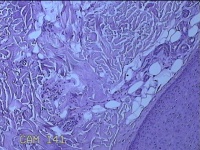

头皮结节

性别

男

年龄

33岁

临床诊断

皮肤赘生物

一般病史

发现头皮结节半个月余,无明显疼痛及不适。

标本名称

大体所见

灰白暗红色带皮肤样结节1x0.8x0.3cm一个,表面糜烂,切开结节呈实性,切面灰白粉红色,质软。

看不清,可能是毛细血管瘤,技术很需提高,不然迟早会。。。